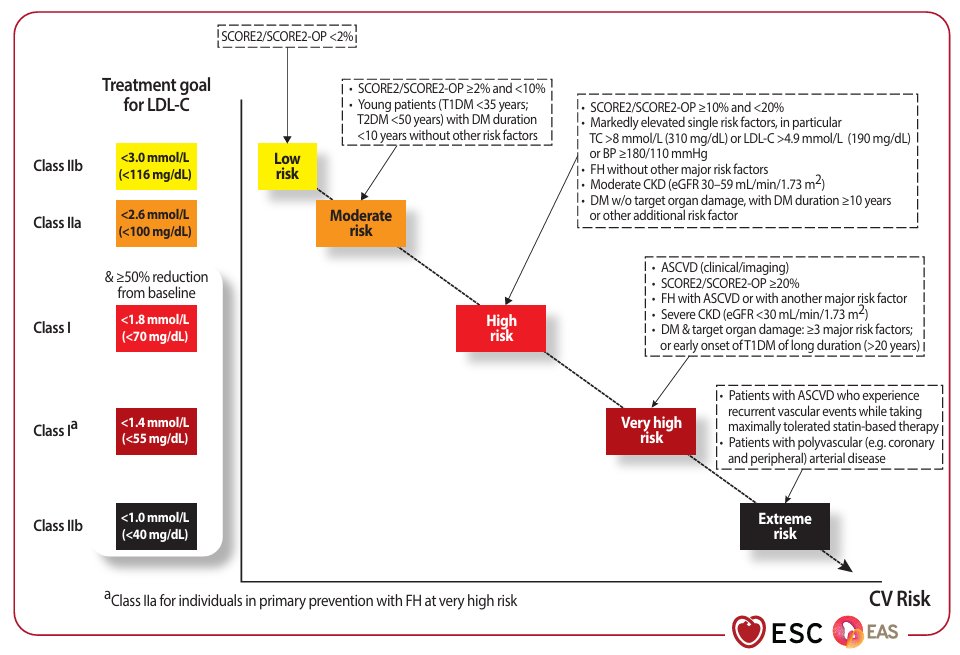

🎯 Objetivos de tratamiento para el colesterol LDL según las categorías de riesgo cardiovascular total👇🏼 #ESC #CardioEd #Colesterol #Prevención #Cardiología #LDL #RiesgoCardiovascular